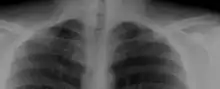

Bilateral, symmetric, full, ossified cervical ribs.

On imaging, cervical ribs can be distinguished because their transverse processes are directed inferolaterally, whereas those of the adjacent thoracic spine are directed anterolaterally.[11]